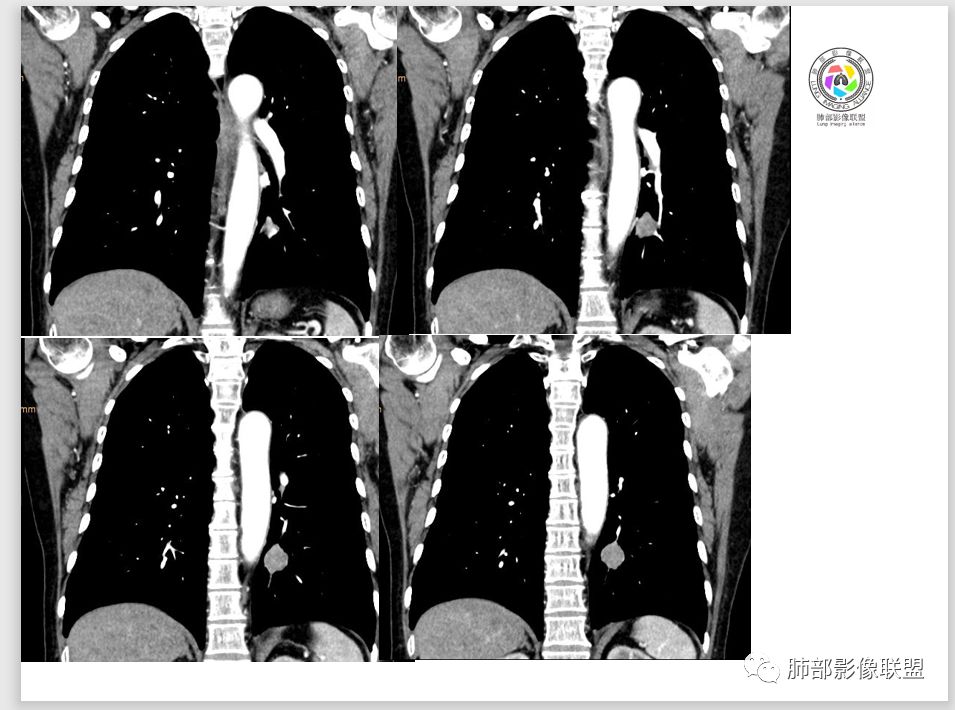

目前大家意见一致一米阳光:左肺下叶类圆形病灶,边缘清晰,密度均匀,无分叶毛刺等恶性征像,增强,病变明显强化,血管贴边支持PSP,鉴别类癌,后者弱强化,貌似有分叶南边:

M-Imaging :周围有黑边,错构呢?南边:如果明确没堵塞就好办这个最主要的就是这个支气管是否堵塞没堵塞,支持PSP杨泽锋:如果是气管腔内起源的那就要考虑类癌M-Imaging :不见明显冰山征,没有钙化南边:心里不是很踏实,就是没看到支气管全景Forever:强化如果不高 我还是考虑小细胞肺癌或者腺癌

Shelia:隆突下没看到肿大淋巴结呀南边:那就是支气管应该是堵了。图少了一点

wonderful:纵膈有吗徐超:隆突下没有肿大淋巴结。思路没问题,主要还是支气管的关系。还有CT值,有测量值最好。强化不同疾病范围不同,虽然有叠加Coke with ice:这个病灶好像有浅分叶,是否有鉴别意义呢南边:可能绕过去了。浅分叶没什么价值,深分叶有Forever:动脉期强化不太均匀 而且ct值不高我觉得有提示意义

而且这例没看见肿大淋巴结

M-Imaging :淋巴结肿大的也不明显。下次看见,还是考虑良性

徐超:小细胞侵袭性强破坏相对没有其他癌肿强,血管和支气管破坏较晚。强化也较弱。截断罕见,阻塞的也很少,一般挤压狭窄多。